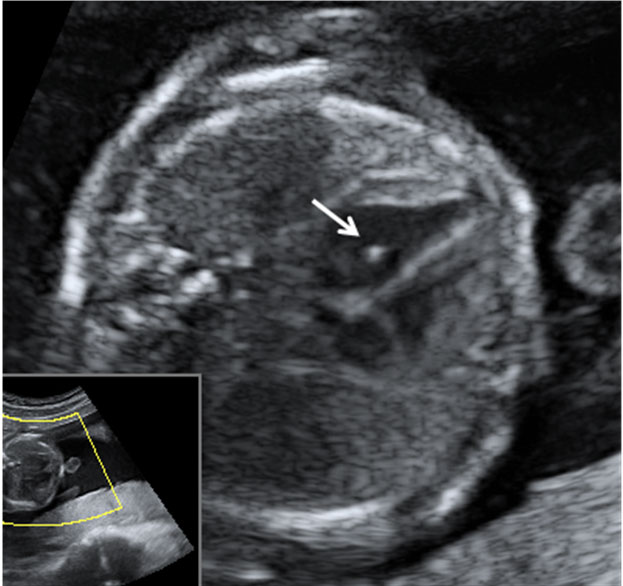

A esta edad temprana, apenas 20 semanas de gestación, las estructuras faciales básicas están prácticamente conformadas.

Ecografía Embarazo 2D y 3D Semana 20 - MALFORMACIONES FETALES